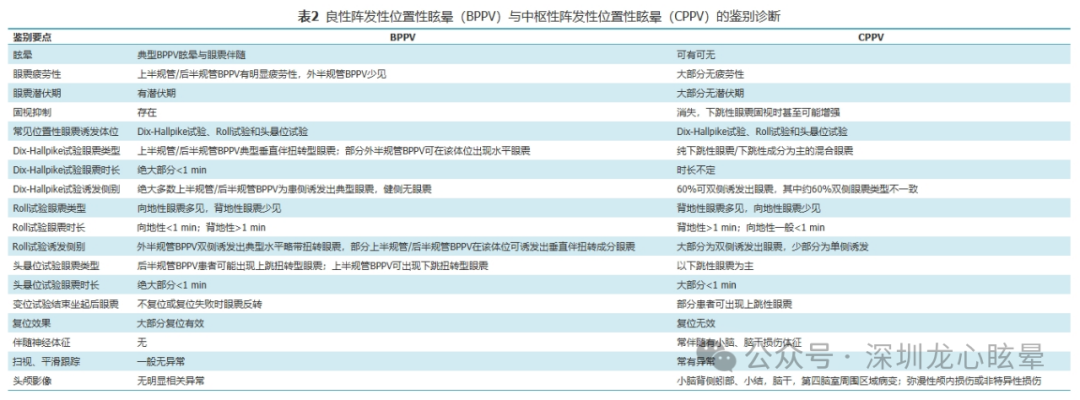

CVIV 大多为供应小脑和脑干的椎-基底动脉系统缺血或出血性病变所致,而以脑梗死最为多见。小脑出血引起的血管源性头晕/眩晕:小脑出血多表现为严重急性眩晕发作,伴头痛、恶心呕吐及严重姿势平衡障碍,大约50%的患者在发病24 h内意识丧失,75%的患者在发病1周内昏迷。脑干出血引起的血管源性头晕/眩晕:脑桥大量出血者初始症状可表现为眩晕、头痛及呕吐,症状进展可导致四肢瘫、去脑强直、异常水平眼动、眼球浮动、针尖样瞳孔乃至昏迷;原发性延髓出血较为少见,表现为突发性眩晕、头痛、恶心呕吐及吞咽构音障碍,严重者可出现心肺功能衰竭。动静脉畸形所致的脑出血则影像学表现相对重,而症状轻微。颅脑CT影像学检查是快速识别小脑/脑干出血最有效的方法。

图1 一例小脑出血